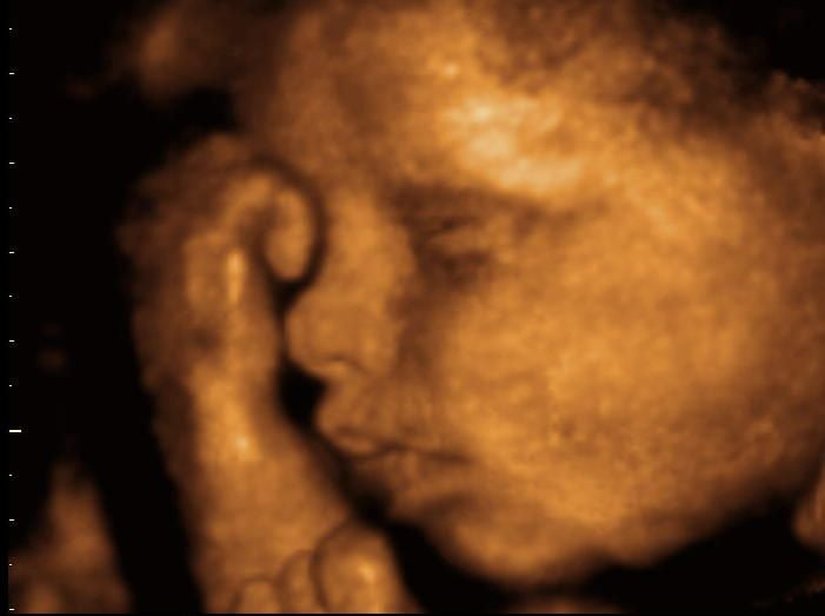

Ama giderek popülerleşen bir teknoloji sayesinde ebeveynler artık yavrularını çok daha net görebiliyorlar: 3D ve hatta 4D ultrason! Monako'daki Princes Grace Hastanesi'nde görev yapan Dr. Bernard Benoit, uzun yıllardır 3 boyutlu (ve hatta 4 boyutlu) ultrason görüntüleme teknikleri üzerinde çalışıyor ve çok başarılı sonuçlara da imza atmış vaziyette. Aşağıda, bunun bir örneğini görüyorsunuz.

Bu görüntüleme tekniği sayesinde, artık renkli ve çok daha net sonuçlara ulaşabiliyoruz. Bu görseller, bunun en net ispatlarından biri. Ana karnındaki ikizleri çok detaylı bir şekilde görüntülemek artık mümkün. Hem de o, uzaktan odaklanılmış bir kare. Aşağıdakiler, ne demek istediğimizi daha net anlatacaktır:

3D ultrasonlarda, birden fazla açıdan 2 boyutlu görüntüler çekiliyor ve sonrasında bilgisayar yardımıyla 3 boyutlu bir görsele dönüştürülüyor. Bu sayede bebeğinizin sadece bir kesidini değil, 3 boyutlu bir görüntüsünü elde etmeniz mümkün oluyor.

4D ultrasonlarda ise, 3D olan görüntüler zamana yayılmış bir şekilde kaydediliyor. Bu sayede bebeğin hareketlerini tıpkı bir video izler gibi görmeniz mümkün oluyor. Bu sayede bebeğin gözlerini açıp kapaması, gülümsemesi veya parmağını emmesi gibi olayları çok net bir şekilde görüntüleyebiliyorsunuz.